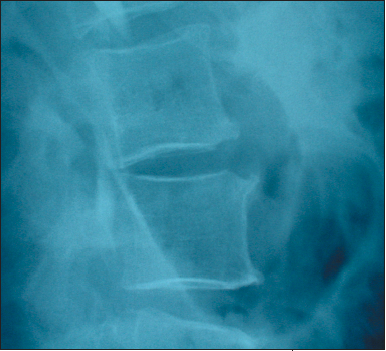

The patient was afebrile. Examination revealed tenderness in the left mid abdomen, left lower quadrant, and left costovertebral angle. Neurologic findings were normal. A lateral lumbar spine radiograph showed an abnormality at the L2-3 level, which suggested diskitis. A CT scan of the abdomen confirmed the diagnosis. There was no evidence of cord compression.

Vertebral osteomyelitis/diskitis is frequently diagnosed late. Often, patients have symptoms for weeks or months before plain films show evidence of bone inflammation or loss of disk height. Fever and elevated WBC counts are variable findings.